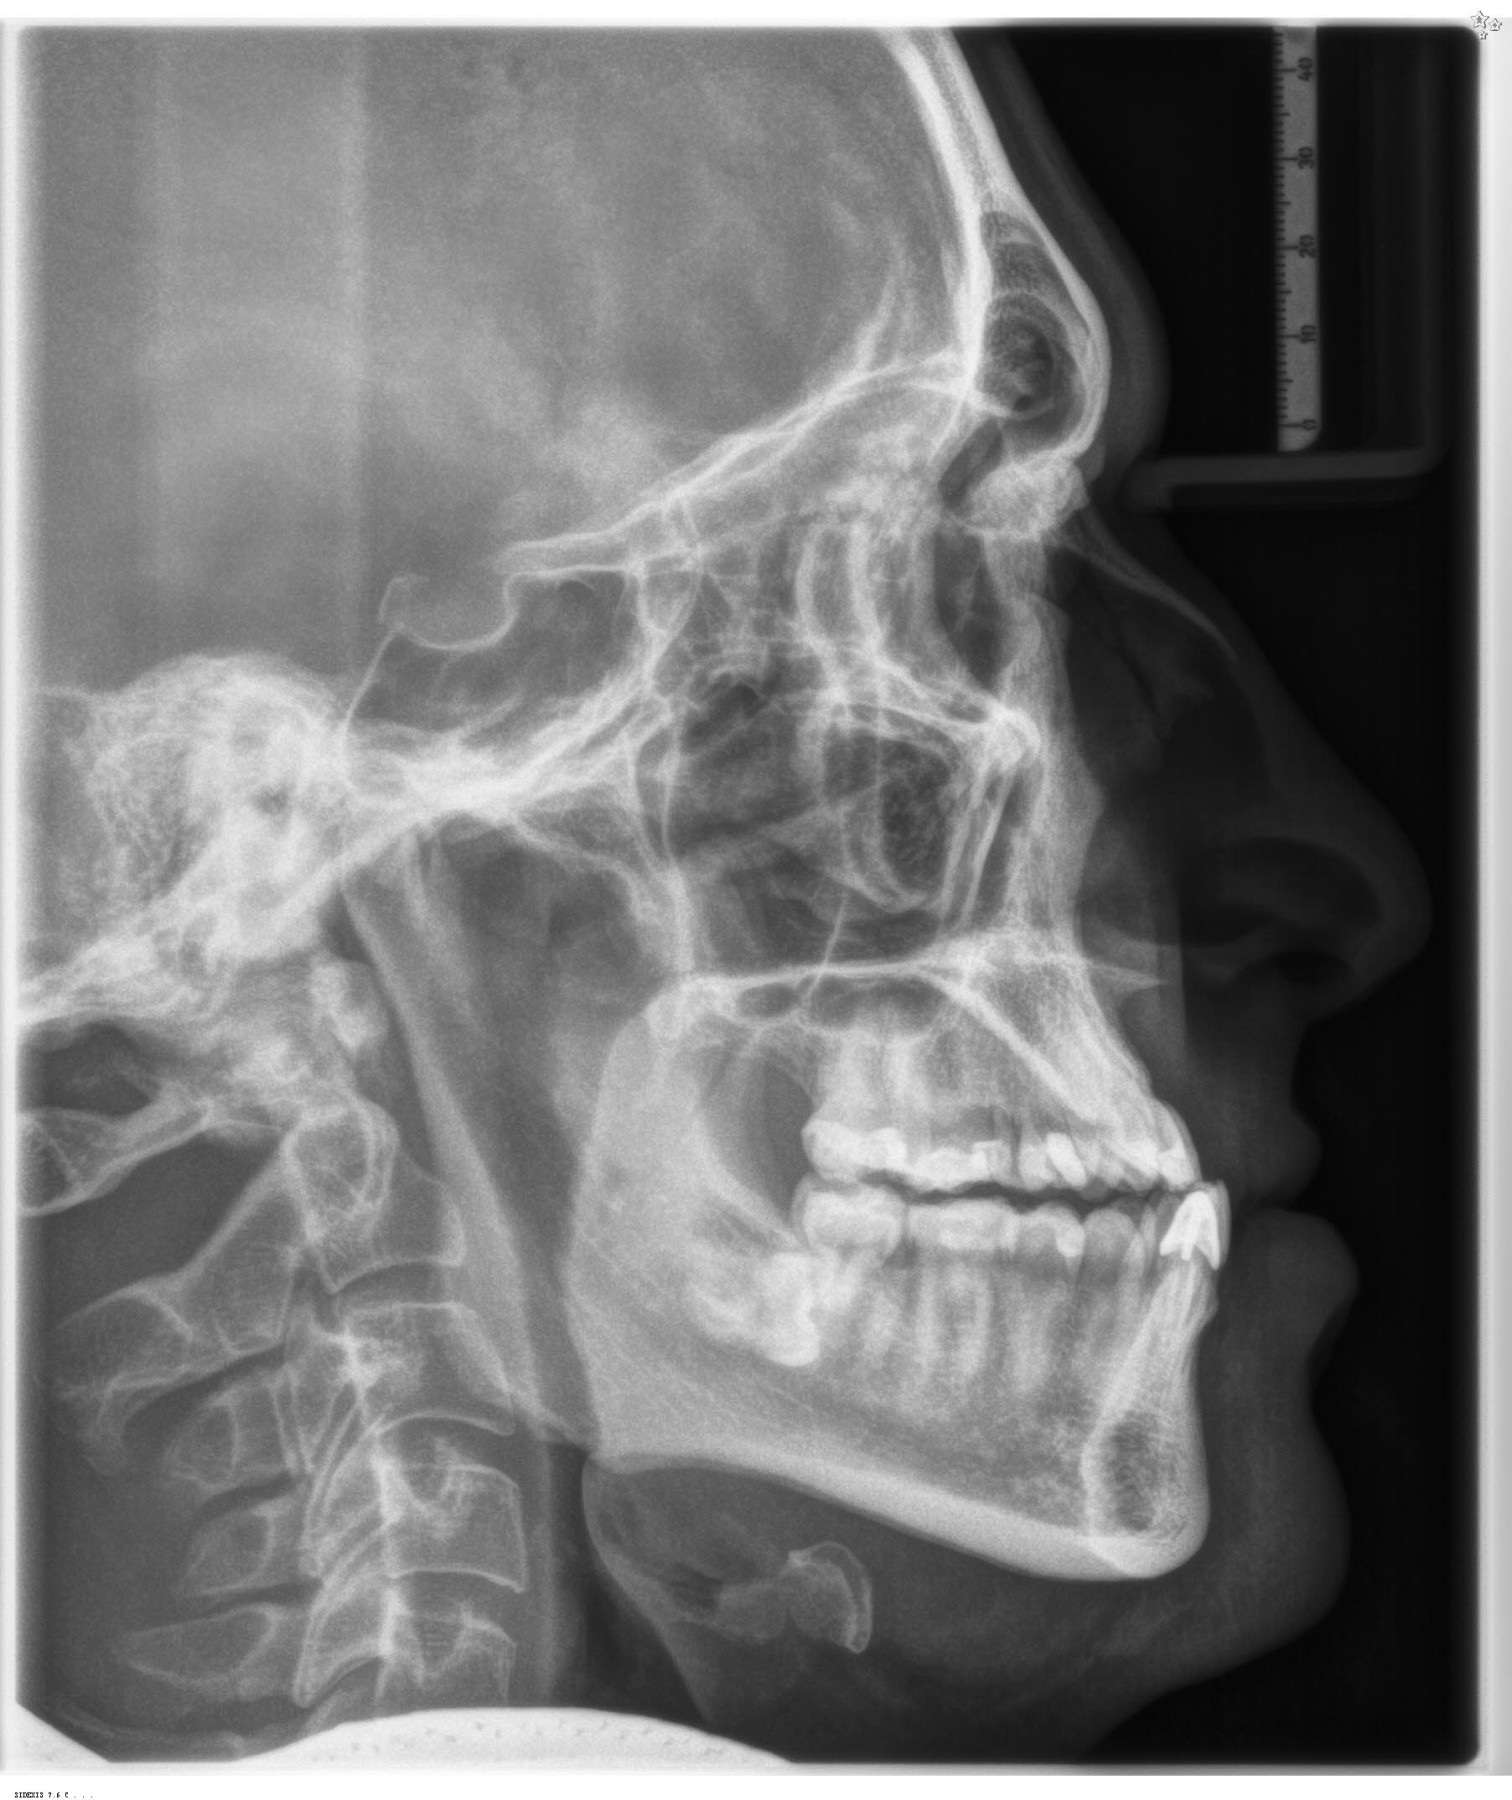

Kieferorthopädische Diagnostik ist das A & O

Erwachsene, die sich für eine kombinierte Therapie entscheiden, stehen meist im Berufsleben und für sie ist das Zeitmanagement und der Ablauf der Therapie besonders wichtig. Voraussetzung für die exakte Diagnoseerstellung ist eine ausführliche kieferorthopädische Diagnostik. Nach Auswertung der diagnostischen Unterlagen wird ein medizinisches Behandlungskonzept durch den Kieferorthopäden erstellt, das der gesetzlichen Krankenkasse (GKV) zur Genehmigung vorgelegt werden muss. Zusätzlich erfolgt die Untersuchung und Beurteilung durch einen Mund-, Kiefer- und Gesichtschirurgen vor Behandlungsbeginn. Die Stellungnahme des Chirurgen ist gleichzeitig Voraussetzung für die Genehmigung bei der Krankenkasse (GKV). Meist werden die Unterlagen zusätzlich von einem Gutachter beurteilt.

Um ein optimales Gesamtergebnis zu erzielen, müssen Kieferorthopäde und Kieferchirurg eng zusammenarbeiten. Nach der gemeinsamen Planung der individuellen Therapie stimmen sie ihr jeweiliges Vorgehen detailliert aufeinander ab. Heutzutage kann die operative Korrektur skelettaler Kieferfehllagen dank modernster digitaler Technik hochpräzise geplant werden. Neben 3D-Röntgenbildern mittels digitaler Volumentomografie (DVT) ist dabei auch der Eingriff komplett virtuell planbar.